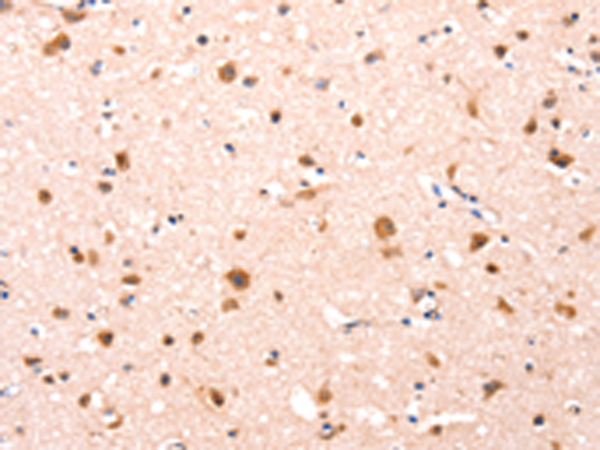

分类: 科研抗体货号: P10843别名: HB5; HVH8; HVH-5; C11orf81应用: WB,IHC反应种属: Human, Mouse